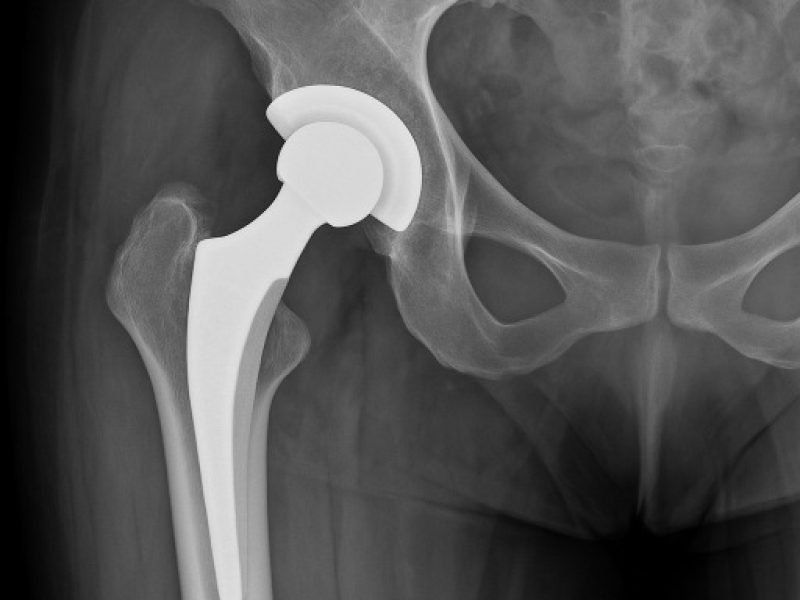

We offer advanced hip replacement surgery using minimally invasive techniques and modern implant technology to reduce pain and restore mobility.